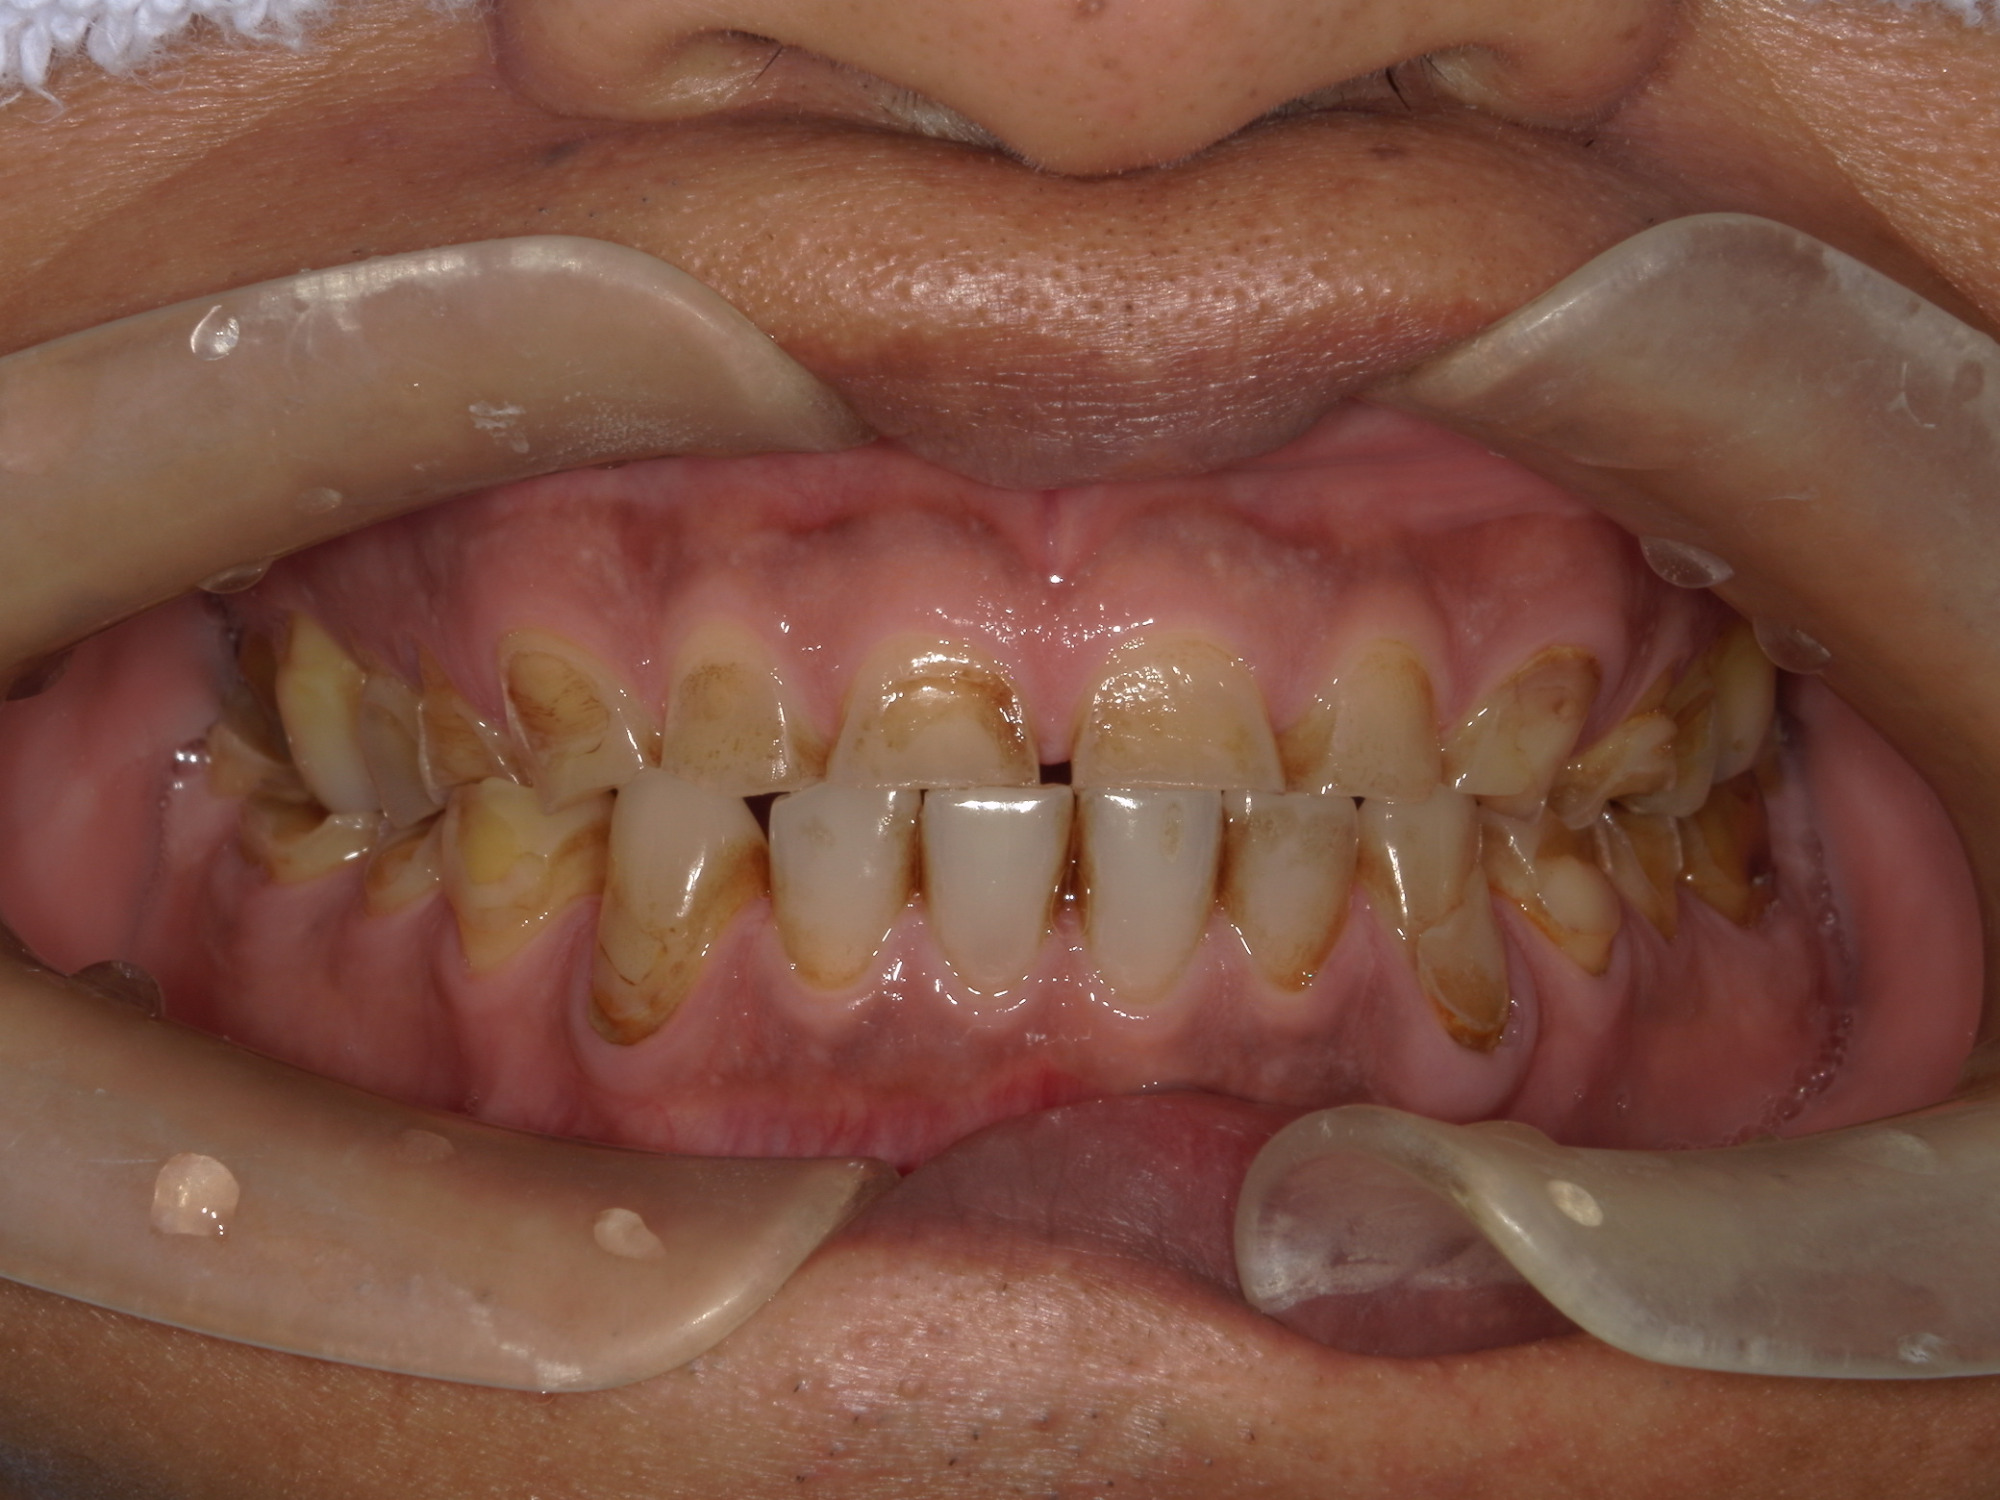

全顎的なセラミック治療によって、審美及び機能咬合回復を行った症例

患者様情報 40代男性 患者様のお悩み 見栄えが気になる、噛み合わせが気になる 治療概要 詰め物・被せ物 提案内容 全顎的に歯が噛耗しており審美的にも、機能的にも改善が必要な状態であった為、全顎的な補綴治療を提案させてい […]